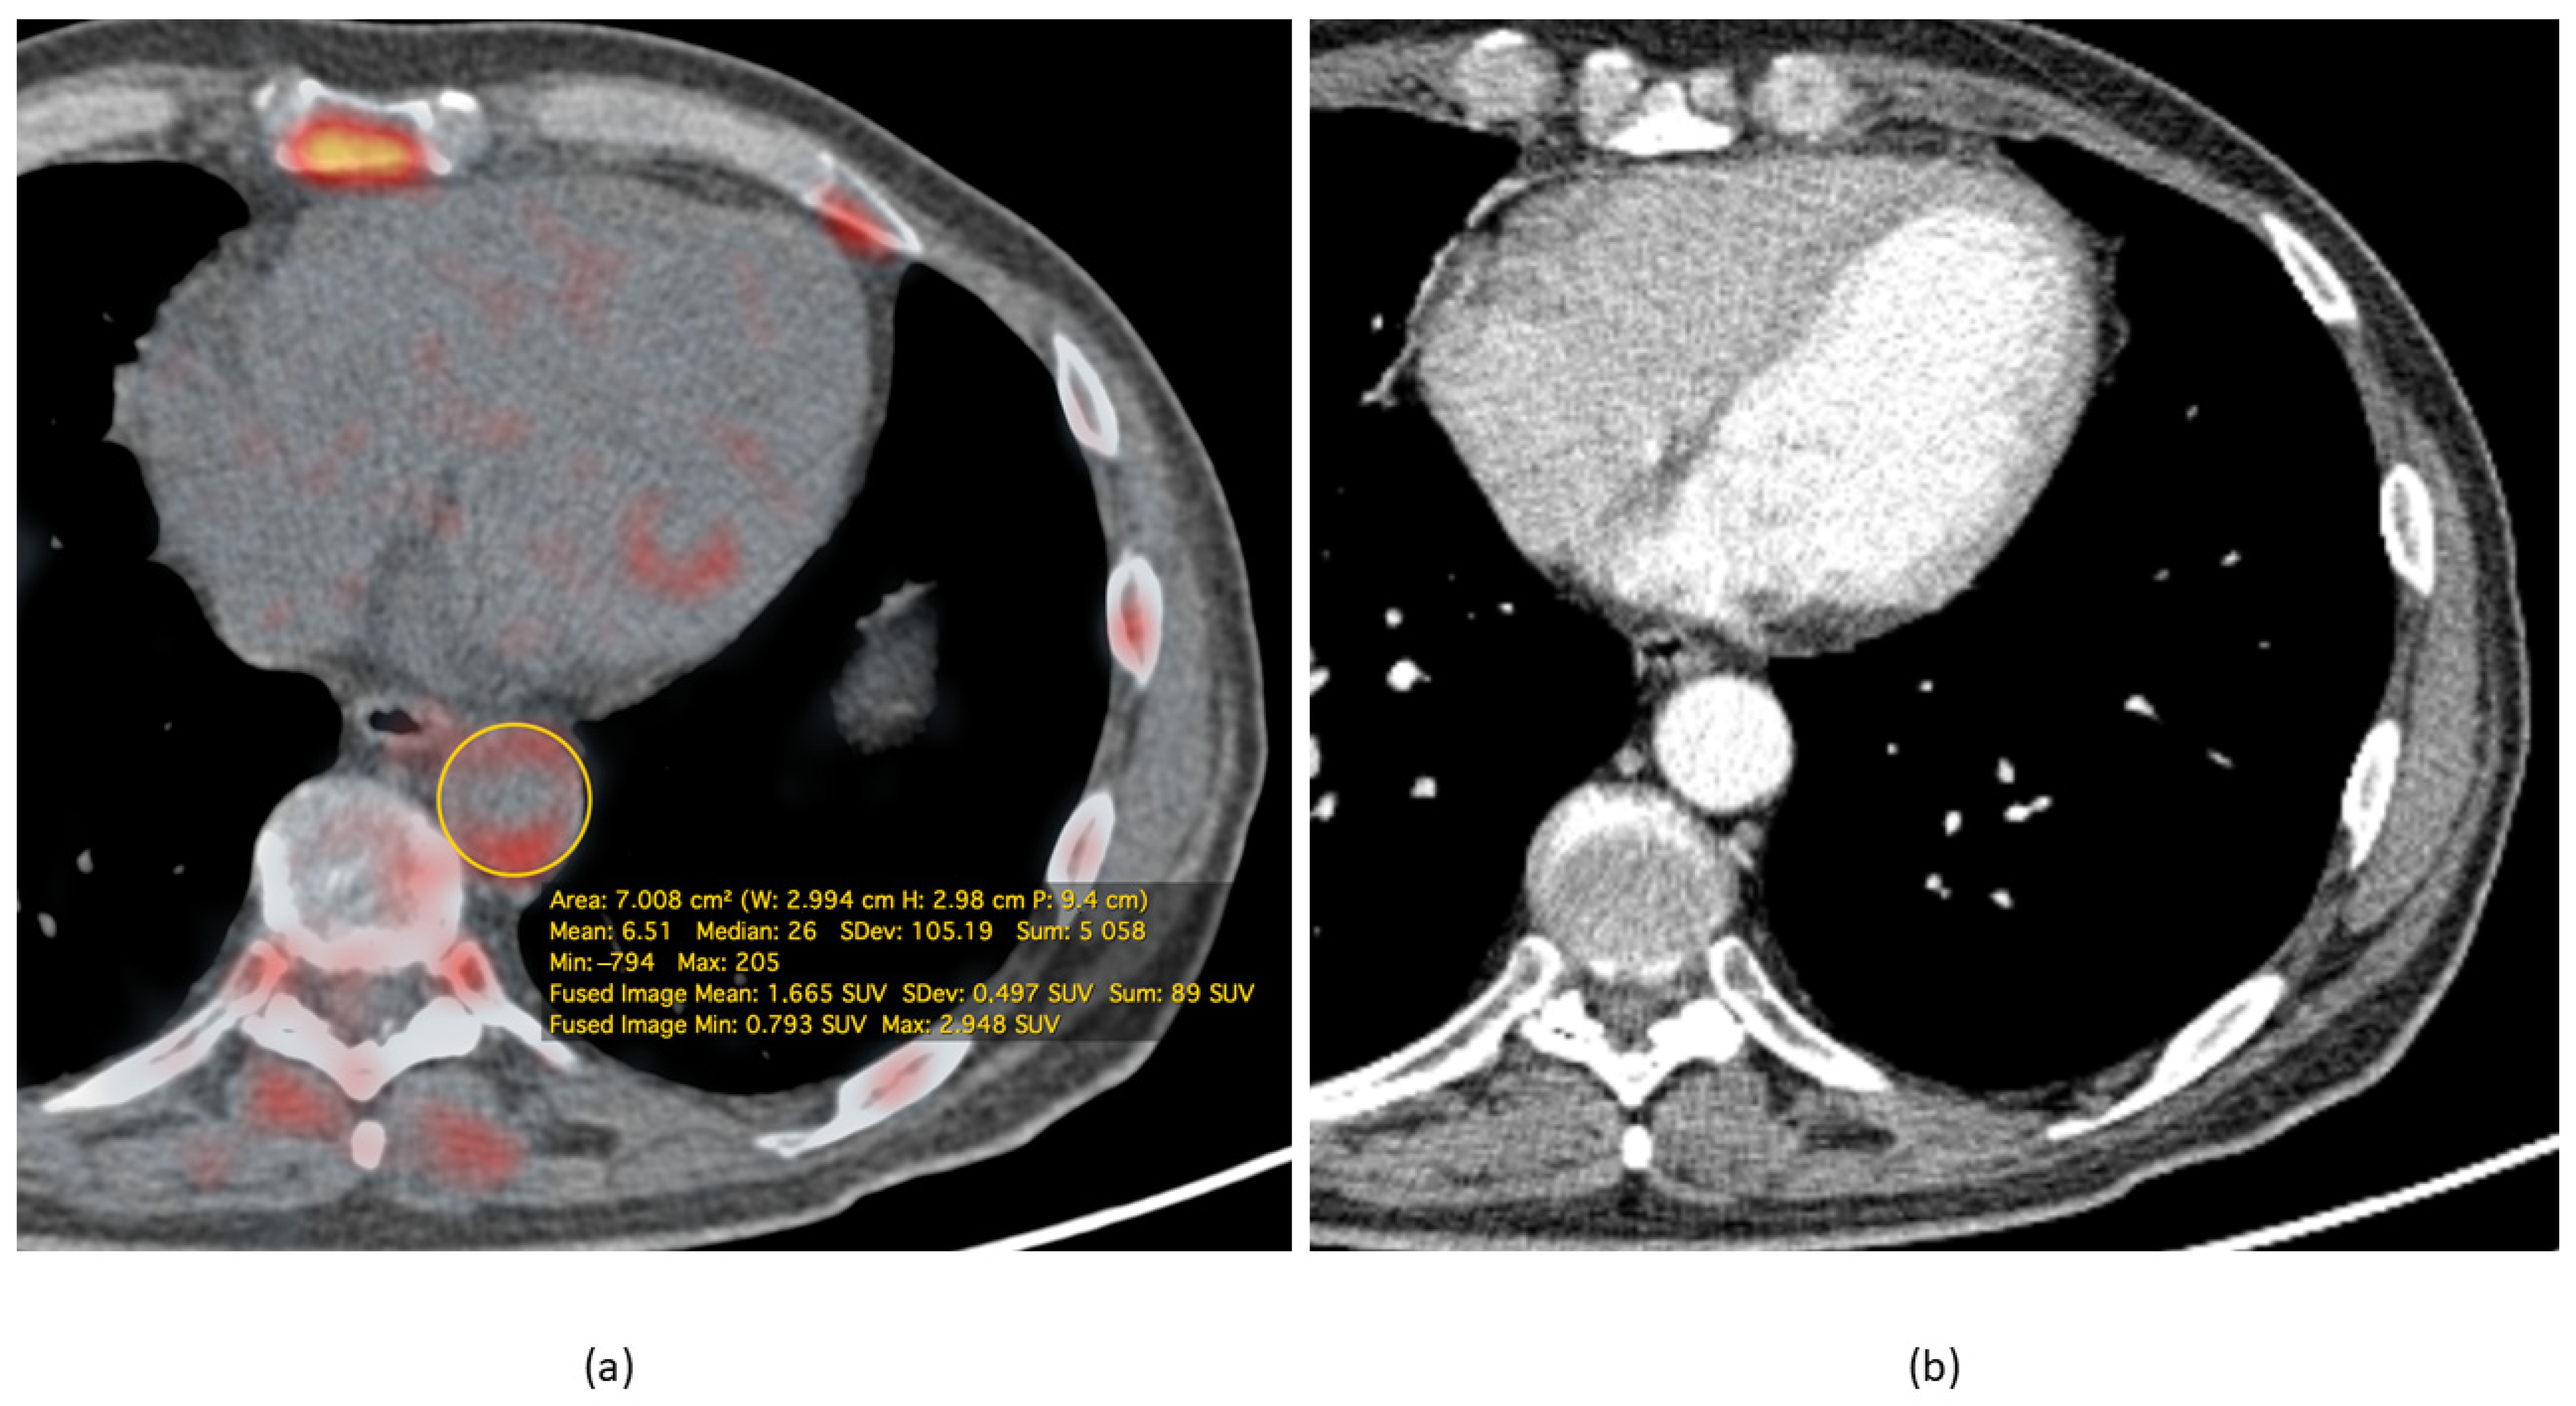

- Koa, B.; Borja, A.J.; Yellanki, D.; Rojulpote, C.; Tran, J.; Zhang, V.; Werner, T.J.; Alavi, A.; Revheim, M.-E. 18F-FDG-PET/CT in the assessment of atherosclerosis in lung cancer. Am. J. Nucl. Med. Mol. Imaging 2021, 11, 1–9. [Google Scholar]

- Rominger, A.; Saam, T.; Wolpers, S.; Cyran, C.C.; Schmidt, M.; Foerster, S.; Nikolaou, K.; Reiser, M.F.; Bartenstein, P.; Hacker, M. 18F-FDG PET/CT Identifies Patients at Risk for Future Vascular Events in an Otherwise Asymptomatic Cohort with Neoplastic Disease. J. Nucl. Med. 2009, 50, 1611–1620. [Google Scholar] [CrossRef] [PubMed]